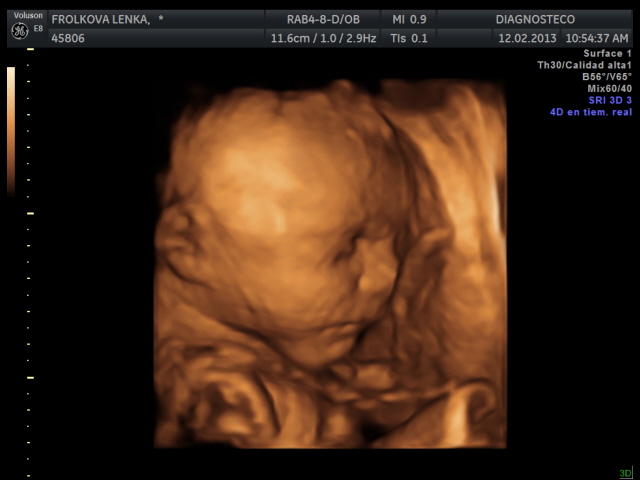

Manolito se nam vcera pretocil hlavickou nahoru a kouka na pater, takze nebyl moc videt, 4D utz zopakneme za 14 dni. Ale zatim mame nejakou tu fotecku a aji video, jen ne tak kvliatni.

Manolito uz vazi 1300 g a meri 36 cm. Ma cumacek po manzelovi a nosanek asi spis po me.